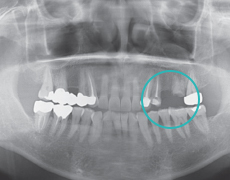

Дооперационный осмотрОпределяется диагноз, устанавливается план лечения.

Первичная процедура (установка импланта)Иплантант размещается в углубление, предварительно сделанное в кости.